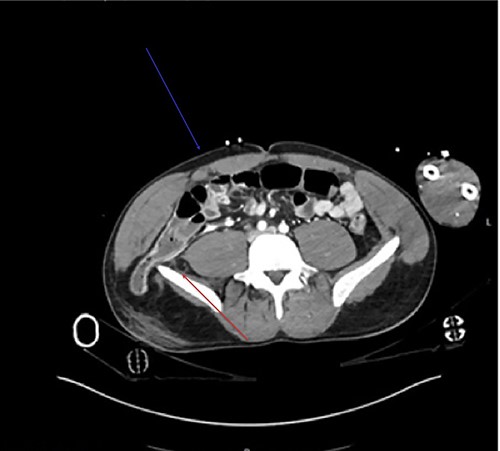

Traumatic lumbar hernias are quite uncommon, as such most surgeons are unfamiliar with them. This was a 41-year-old male Caucasian who was involved in a head on vehicular collision of estimated velocity of 140 mph. Computed tomography (CT) trauma scan confirmed a lumbar hernia through the inferior triangle of petit containing the ascending colon (Figs 1–3). Multiple bony fractures were also noted on the imaging. In discussion regarding the management of the hernia, it was felt that urgent repair was needed to avoid bowel ischaemia or perforation, rather than delayed repair. To repair the defect a laparoscopic approach was initially trialled, (transabdominal repair). Peritoneum was incised around the hernial defect to access the extra-peritoneal space. The hernial sac was dissected; bowels showed no macroscopic signs of ischaemia or injury in the sac. However there was major avulsion of muscles from the iliac crest (>15-cm defect; Fig 1), which was closed posteriorly. Anteriorly it was difficult to close the defect as it was difficult to suture the muscles on to the periosteum of the iliac crest. A decision was made to convert to open surgery as to better access the muscles for suturing. Ventralight mesh was placed extra-peritoneally for further enforcement. The right inferior epigastric vessels were also notably torn, which were tied. Torn right rectus muscles were also approximated and sutured. Peritoneum was closed. This repair was performed extra-peritoneally.

Axial view of the CT demonstrates the tear in the rectus muscle (blue arrow). Inferior lumbar hernia can be clearly demonstrated, above the iliac crest (red arrow).